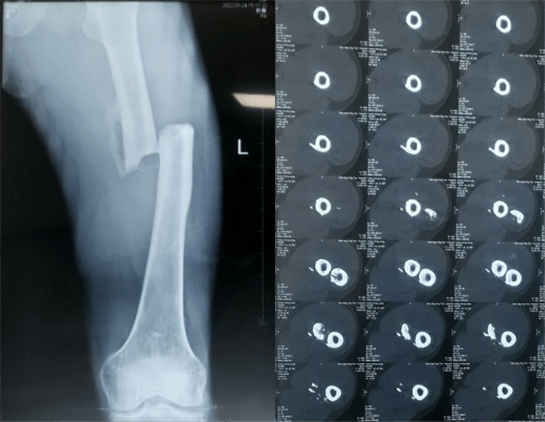

患者:男性,43歲,左股骨干骨折髓內釘內固定術

醫院:南京應天骨科醫院

股骨是下肢的主要負重骨,有其特殊的解剖關系,周圍肌肉發達,因此一旦股骨干骨折后如果治療不當,容易造成肌肉牽拉,導致畸形和功能障礙。治療股骨干骨折,必須遵循恢復肢體的長度及力線,無旋轉,盡量行以微創,保護骨折局部血運,促進愈合。髓內釘對骨折的固定能夠達到較大的穩定性和堅固性,可以減少醫源性污染,減少軟組織分離及周圍血供破壞,有利于骨折早期愈合,是治療股骨干骨折的首要治療方法。

術前檢查